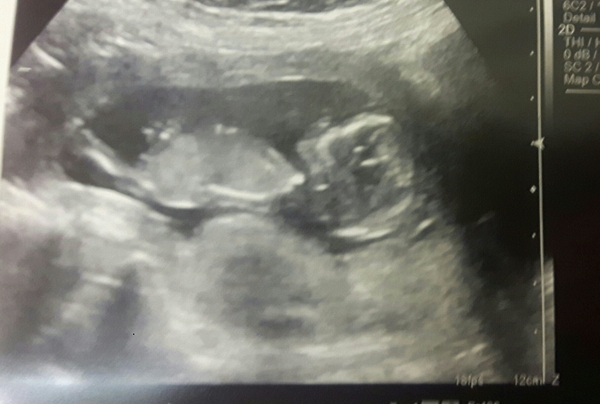

Skull/nub theory - any guesses please

Just curious on people's thoughts?

I'm very confident that you're having a girl x

@MrsH2618 Baby's nub looks like a girl and baby's skull looks like a girl. I'll attached my 12 week scan and you can see my boy skull isn't as round and boy nub sticks upwards more. I'm 23 weeks and definitely having a boy.

Hiya, nub is a bit harder to see here but if I guessed by skull I would definitely still say a little girl Smile